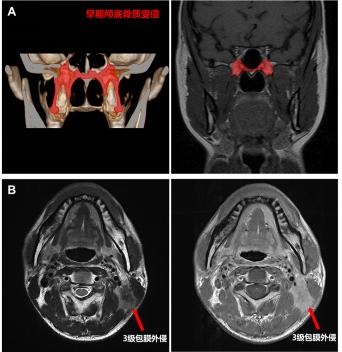

隨著核磁共振技術的發展,鼻咽癌早期顱底骨質受侵(僅翼突或蝶骨基底受侵)患者的檢出率顯著提高,占到所有患者的10-20%,原發灶分期為T3患者的20-30%。既往研究報道早期顱底骨質受侵患者預后較好,或可豁免高強度的化療。本次研究結果顯示,早期顱底骨質受侵的T3患者的5年生存率為91.9%,顯著優于其余T3患者(88.8%),且與T2患者相似(91.5%)。因此,建議將輕度顱底骨質受侵降為T2。

頸部嚴重淋巴結包膜外侵(即3級包膜外侵,腫瘤突破淋巴結包膜侵犯淋巴結周圍鄰近結構)患者往往臨床預后較差,治療后極易發生復發轉移。研究發現原淋巴結分期為N1和N2患者中嚴重頸部淋巴結包膜外侵患者5年生存率分別為82.0%和77.1%,與N3的78.7%接近。因此,建議嚴重頸部淋巴結包膜外侵升級為N3。

新版鼻咽癌解剖結構調整示意圖

A早期顱底骨質受侵:僅有翼突或蝶骨基底的顱底骨質受侵

B 3級淋巴結包膜外侵:腫瘤突破淋巴結包膜侵犯淋巴結周圍鄰近結構